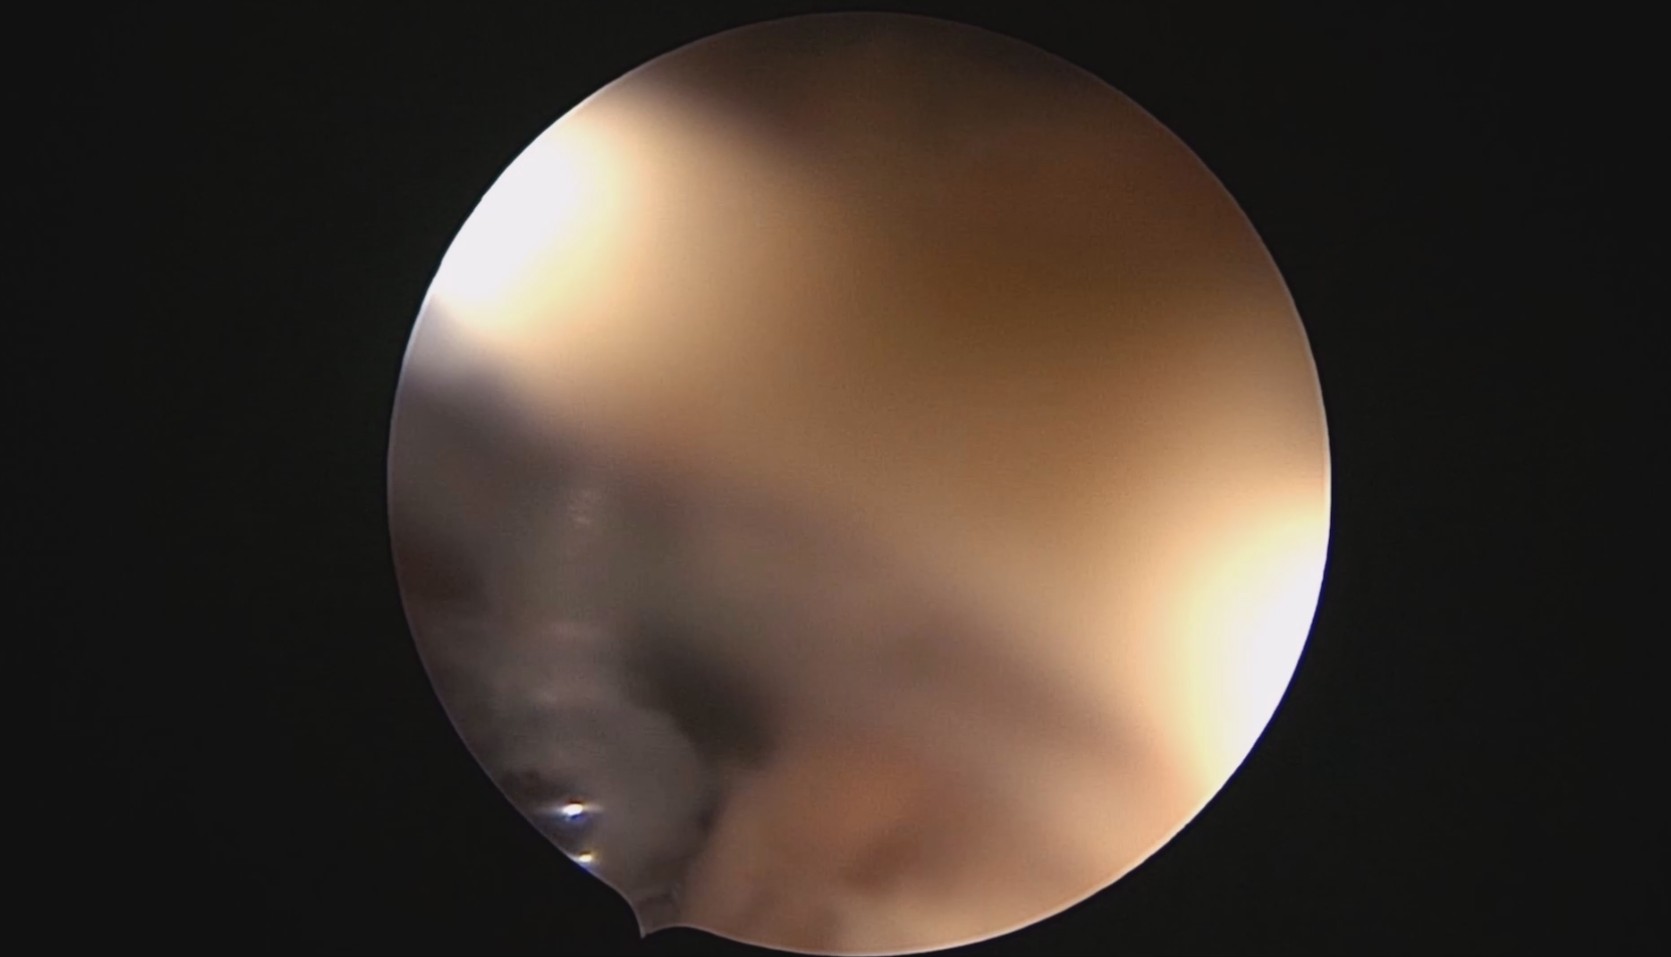

患者28岁,G7P3,顺产3次,完全纵膈子宫,单宫颈。2015年、2018年顺产,2019年左侧宫腔计划外妊娠行宫腔镜取胚及左侧宫腔放置γ环(推测既往妊娠左侧宫腔妊娠可能性大)。2023年4月带环受孕(应该为右侧宫腔妊娠),2023年12月足月阴道分娩,分娩时试图取出左侧宫腔内节育器,因操作困难,取环失败。2024年2月顺产后67天,要求取出宫内节育器,左手臂放置皮埋避孕棒。B超提示环距宫底1.1cm,环两翼分别距子宫前壁浆膜面0.4cm,距子宫后壁浆膜面0.3cm。宫腔镜术中膨宫困难,见宫颈管及宫腔少许淡黄色脓液流出,γ环逆时针旋转约80度,两臂指向左侧宫腔前后壁(2019年放置环时亦如此,因单侧宫腔前后径大于横径所致)。异物钳取出节育环,左右侧宫腔均见散在黄色机化组织,未取病检。